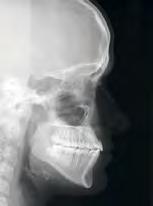

RESULTADOS NOTABLES

Radiografía Clase III

Antes

Después

Imágenes cedidas a Dynaflex por el Dr. Andy Hayes de St. Louis MO